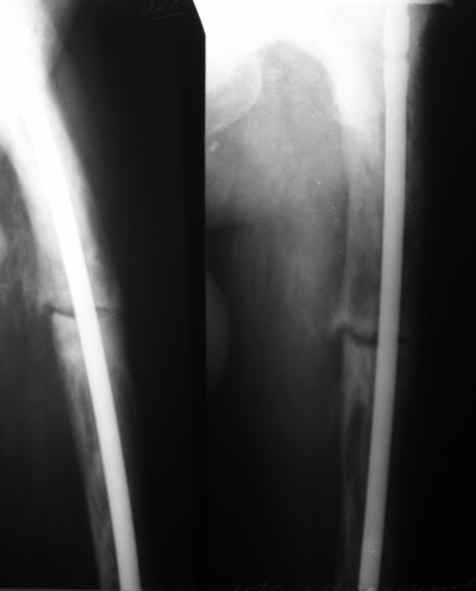

Пациент 82 лет, поступил через 5 мес. с несросшимся переломом после

открытого интрамедуллярного остеосинтеза. Выполнили реостеосинтез

стержнем 12 мм. ( мах. доступного нам в 2003 г.) Через 4 мес

динамизация. В течении 2х лет сращения нет, тем не менее конечность

опорна (ходит с тростью). От очередного реостеосинтеза отказались из-за

сопутств. патологии.